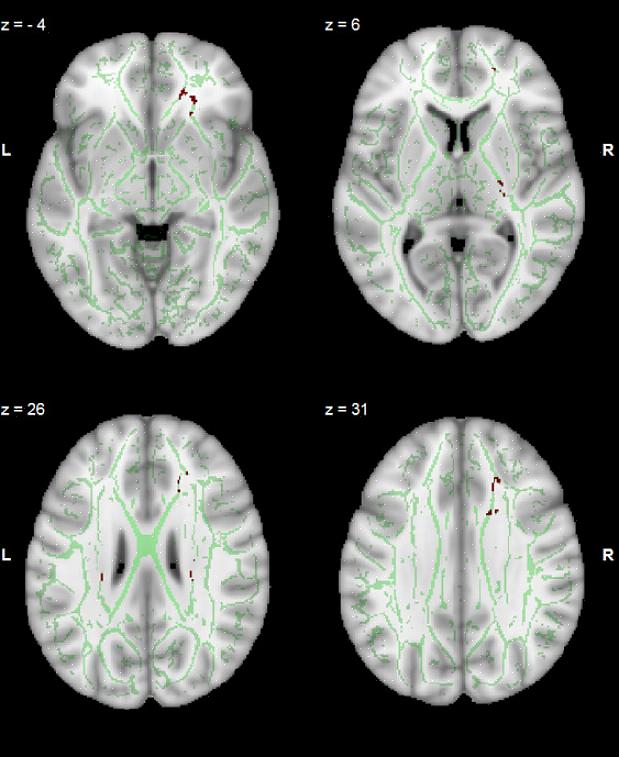

טראומה מופיעה בסריקות מוח ומומחים יכולים כעת לראות אותה ביתר פירוט. לדוגמה, רק לפני מספר חודשים, אוניברסיטת אלברטה בקנדה הציגה מחקר מעניין בנושא זה. הדבר היחיד שהם הגיעו למסקנה הוא שחוויות טראומטיות בין הגילאים ארבע עד שבע פוגעות בהתפתחות המוח התקינה.

צוות המחקר של אוניברסיטת אלברטה הצליח גם לראות כיצד ההיפוקמפוס והאמיגדלה היו האזורים המושפעים ביותר. לפיכך, הדבר הראשון שנראה כאשר טראומת ילדות מופיעה בסריקות מוח הוא שינוי בנפח של אזורים אלה. הם קטנים יותר.

כעת, כאשר מומחים מודעים לכך שטראומה בילדות מופיעה בסריקות מוח, הם מסוגלים לחקור את הסובלים בנפרד ולרשום תרופות מסוימות. לדוגמה, הם גילו שחוויות אלה מאטים לעתים קרובות את הצמיחה של האמיגדלה הבזולטרלי. זה גורם להתנהגות חרדה. במקרים אלו, תרופה חלופית לסרטרלין בשילוב עם טיפול פסיכולוגי ספציפי וממוקד הוא לרוב רעיון טוב.